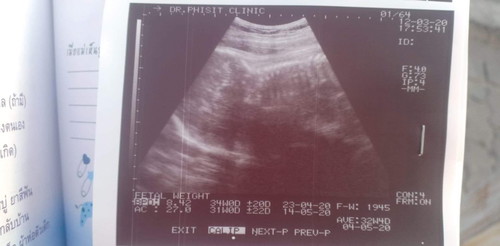

ในภาพน้องนอนคว่ำรึหันหลังให้คะ อิแม่ดูไม่ออก หมอบอกแค่หัวกับกระดูกสันหลัง ?

เหมือนหลังเลยนะคะ